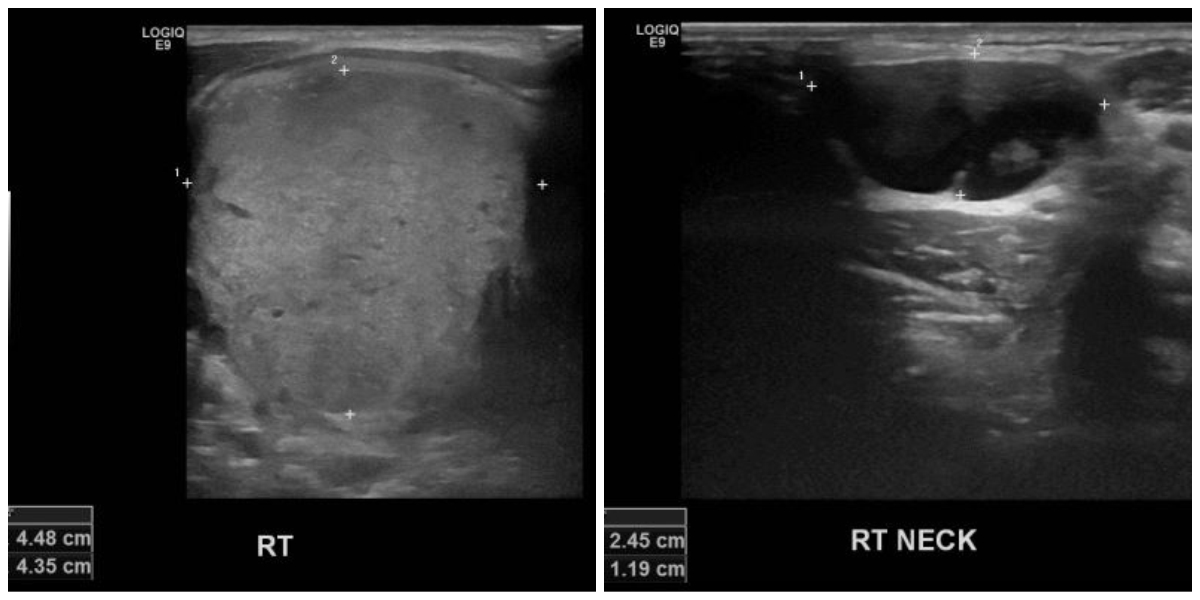

상기환자 우측 목이 튀어나오고 통증있어 내원하신 10대 남성분으로 본원 초음파상 우측

4.48cm  갑상선의 결절과, 우측 목 임파절 2.24cm의 의심스러운 멍울 각각 세침검사 시행하여 우측 갑상선 유두암과, 임파절 전이암 진단 되었습니다.